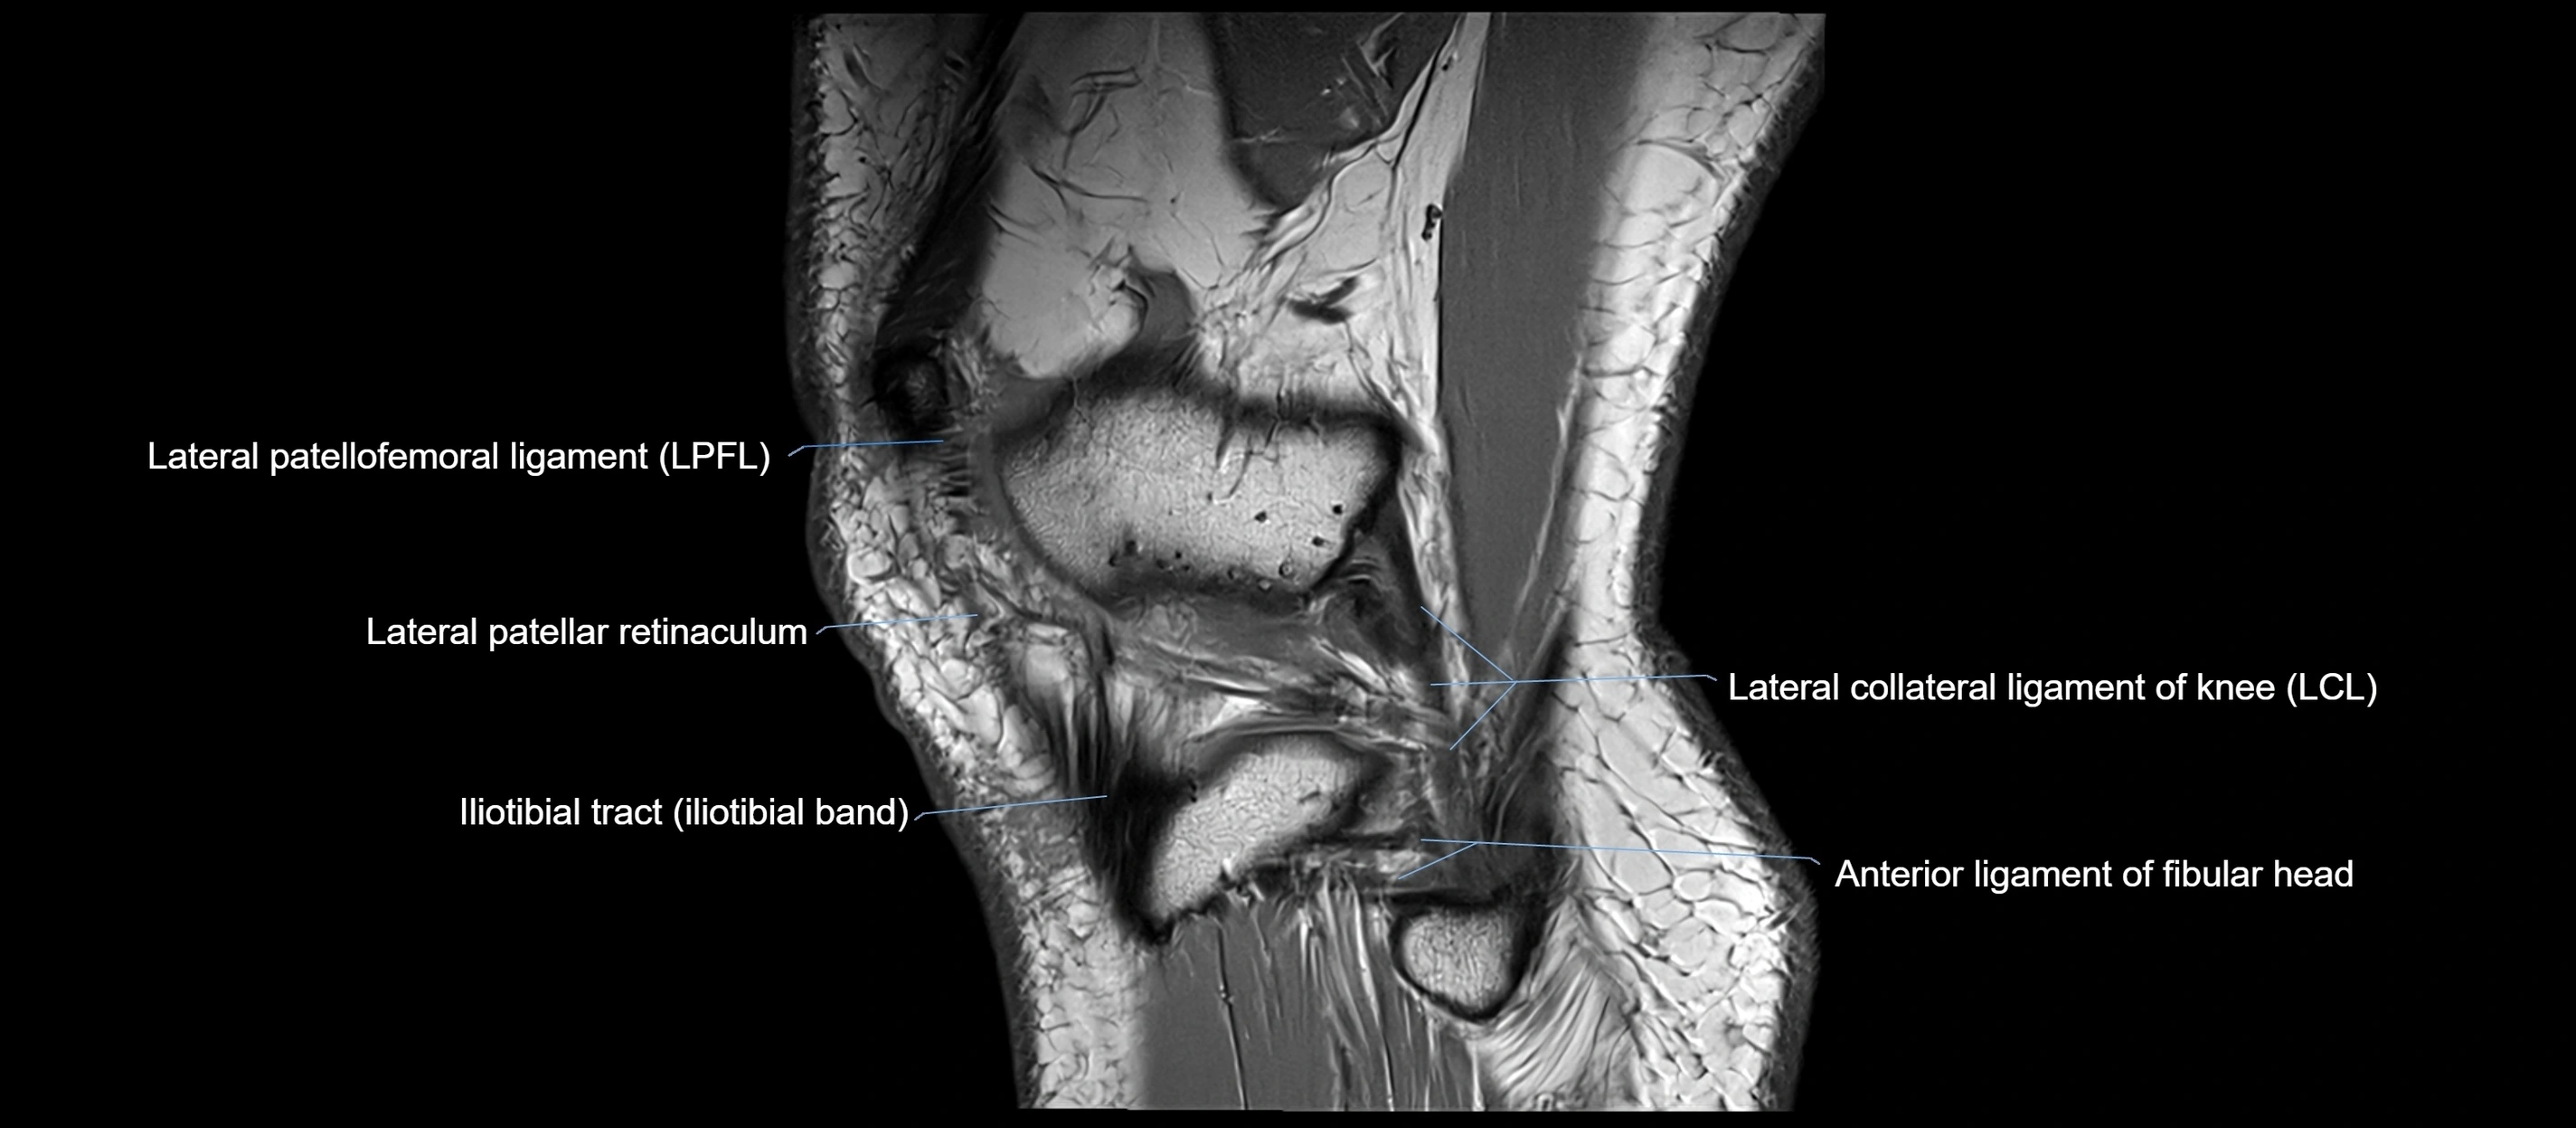

MRI images

image

MRI Appearance

T1-weighted images:

• Normal ACL appears as a low-signal band-like structure crossing the intercondylar notch

• Surrounded by intermediate signal synovial fluid and fat planes

T2-weighted images:

• Normal ACL remains low signal

• Partial or complete tears appear as discontinuity, increased signal, or fiber laxity